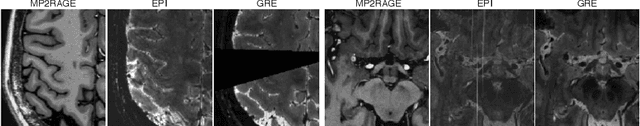

Abstract:The current multiple sclerosis (MS) diagnostic criteria lack specificity, and this may lead to misdiagnosis, which remains an issue in present-day clinical practice. In addition, conventional biomarkers only moderately correlate with MS disease progression. Recently, advanced MS lesional imaging biomarkers such as cortical lesions (CL), the central vein sign (CVS), and paramagnetic rim lesions (PRL), visible in specialized magnetic resonance imaging (MRI) sequences, have shown higher specificity in differential diagnosis. Moreover, studies have shown that CL and PRL are potential prognostic biomarkers, the former correlating with cognitive impairments and the latter with early disability progression. As machine learning-based methods have achieved extraordinary performance in the assessment of conventional imaging biomarkers, such as white matter lesion segmentation, several automated or semi-automated methods have been proposed for CL, CVS, and PRL as well. In the present review, we first introduce these advanced MS imaging biomarkers and their imaging methods. Subsequently, we describe the corresponding machine learning-based methods that were used to tackle these clinical questions, putting them into context with respect to the challenges they are still facing, including non-standardized MRI protocols, limited datasets, and moderate inter-rater variability. We conclude by presenting the current limitations that prevent their broader deployment and suggesting future research directions.